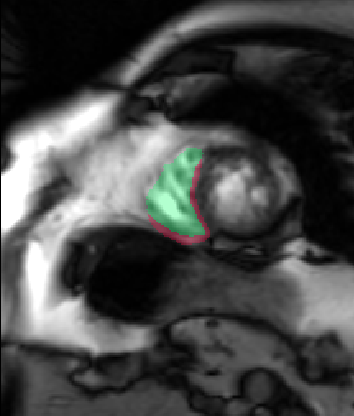

Table 2 summarizes the results of our method for RV segmentation in terms of image-based metrics. The results show that the algorithm performs better at ED than ES. This can be explained by the fact that the image quality is higher at ED than at ES. By analyzing the DM and HD on a slice-basis, it can be seen that the proposed method has a high performance on basal slices, with an average and . However, the segmentations on apical slices are of lower quality affecting the overall DM and HD scores. Figure 3 shows segmentation results in six different cases obtained from the challenge that illustrate the differences between basal and apical segmentations.

The results show that the method perform well on average but there are some cases in which it fails. In particular, our method has a very high performance on the basal slices, whereas the scores obtained for apical slices are lower (Figure 3). These can be explained by two factors: 1) The image quality at the apical slices is rather low. As the registration, the atlas ranking and the label fusion are intensity-based, poor image quality can affect the results, and 2) the regions to be segmented at the apical slices are rather small, which implies that the atlases’ masks are also small at these slices. When the masks are used in the registration process to supress undesired structures, the remaining information is insufficient, causing the intensity-based registration, rigid or non-rigid, to fail.